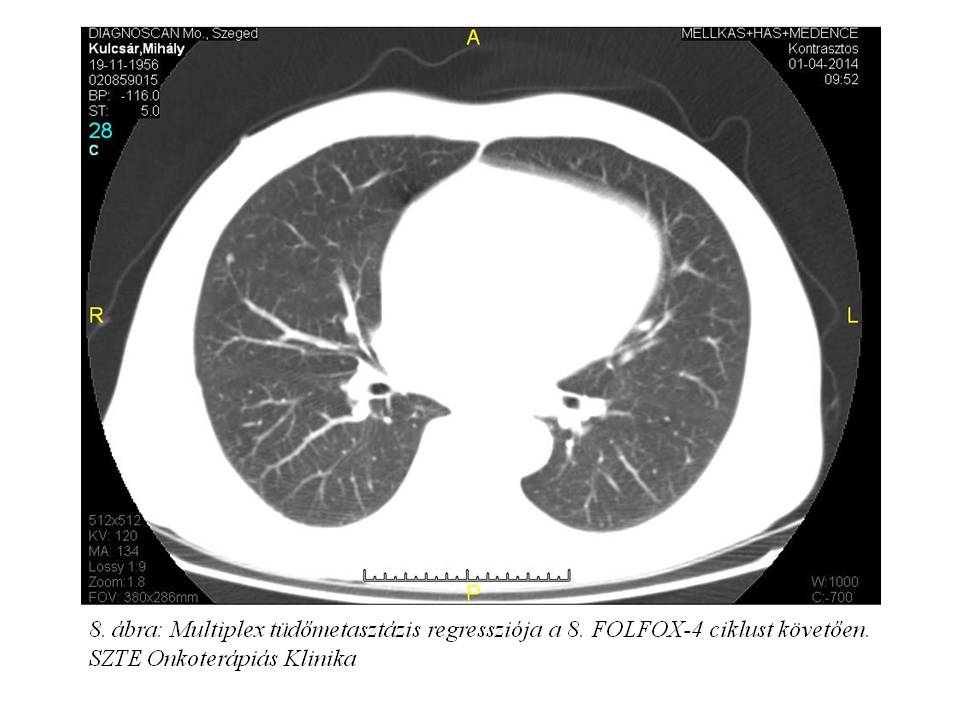

A 8. ciklust követő soros re-staging mellkas, has-kismedence CT-n további regressziót láttunk (2014.04.01., 7. ábra, 8. ábra); a CA 19-9: 27.9 U/ml (normalizálódott), a CEA: 258 ng/ml (megfeleződött). A 9. ciklusra érkezésekor említette először a tenyerek-talpak fokozott hidegérzetét, ekkor még zsibbadás nem volt (oxaliplatin okozta mellékhatásként ismert perifériás sensoros neuropathia). Az oxaliplatin dózisában 1. szintű redukciót alkalmaztunk (75 mg/m2).